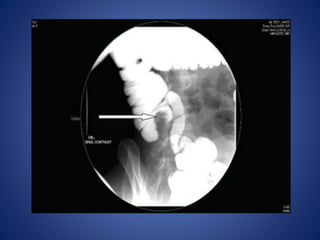

• Barium study Xray (barium enema or barium follow through x-

ray)

– Pulled up caecum, conical caecum, pulled down hepatic

flexure

– Obtuse ileocaecal angle; straightening (Goose neck)

– Steirlin sign: Hurrying of barium due to rapid flow and lack

of barium in inflamed site

– Fleischner sign (Inverted umbrella sign): Narrow ileum

with thickened ileocaecal valve

– Napkin leisons- ulcers and strictures in the terminal ileum

– Increased transient time:Hypersegmentation(chicken

intestine)

– Mega Ileum: Dilatation of proximal ileum

Contrast study

Stricture in ileocaecal region Stricture in descending colon

• Good for intestinal tuberculosis affecting small or large bowel

Barium enema:

• increased (obtuse)

ileocaecal angle

• retracted, fibrosed

caecum (“goose neck

deformity”) ;